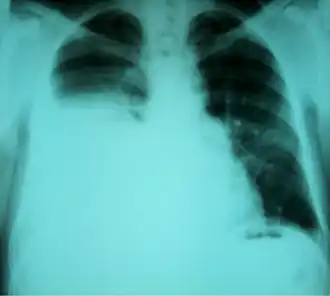

| Radiografia torácica mostrando um hidrotórax hepático em uma pessoa com cirrose | |

Hidrotórax hepático é uma forma rara de derrame pleural que ocorre em pessoas com cirrose hepática. É definido como um derrame de mais de 500 mL em indivíduos com cirrose hepática, não causado por doenças cardíacas, pulmonares ou pleurais. A condição é encontrada em 5–10% das pessoas com cirrose hepática e em 2–3% dos casos de derrames pleurais. Em casos de cirrose hepática descompensada, a prevalência pode chegar a até 90%.[1] Mais de 85% dos casos ocorrem no lado direito, 13% no lado esquerdo e 2% em ambos os lados.[2] Embora seja mais comum em pessoas com ascite grave, também pode ocorrer em indivíduos com ascite leve ou ausente. Os sintomas não são específicos e geralmente envolvem o sistema respiratório.